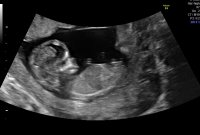

Lille bamsemums har nå blitt en minibaby ❤️ 10 uker i dag og alt ser fortsatt helt fint ut og vokser akkurat som hen skal :)